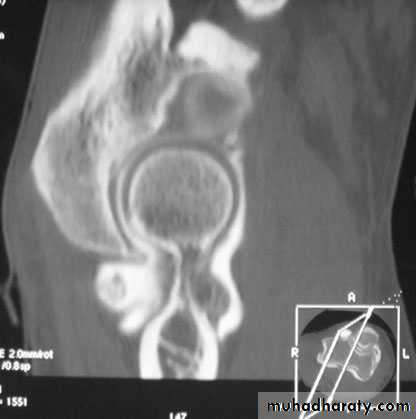

The elbow is affected in about 10%

Clinical features:The onset is insidious

Long hx of aching and stiffness.

The most striking physical sign is the marked Wasting

the joint is held flexed, looks swollen, and feels warm and diffusely tender; movement is considerably limited

X-rays:

peri-articular osteoporosis and joint erosion.

subchondral cystic lesions.